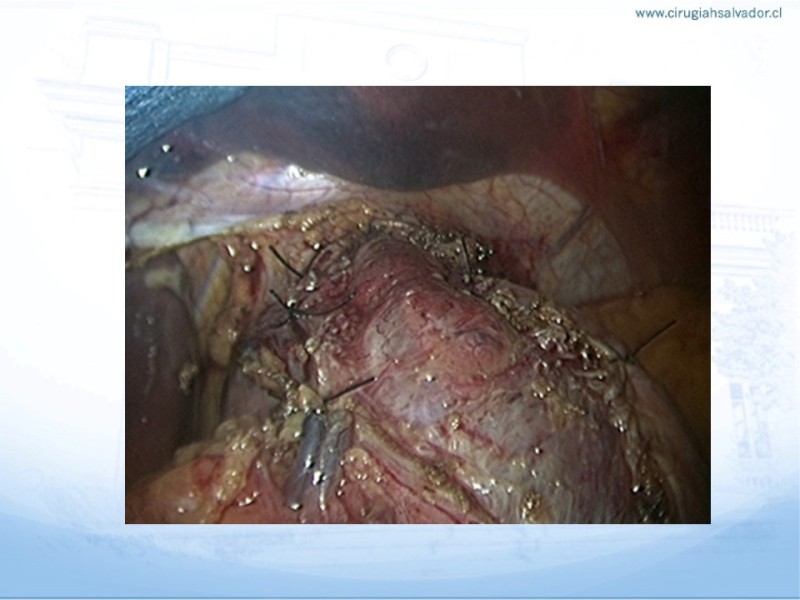

Acalasia

Digestivo Alto

| Autor: Dr. Byron San Martín García